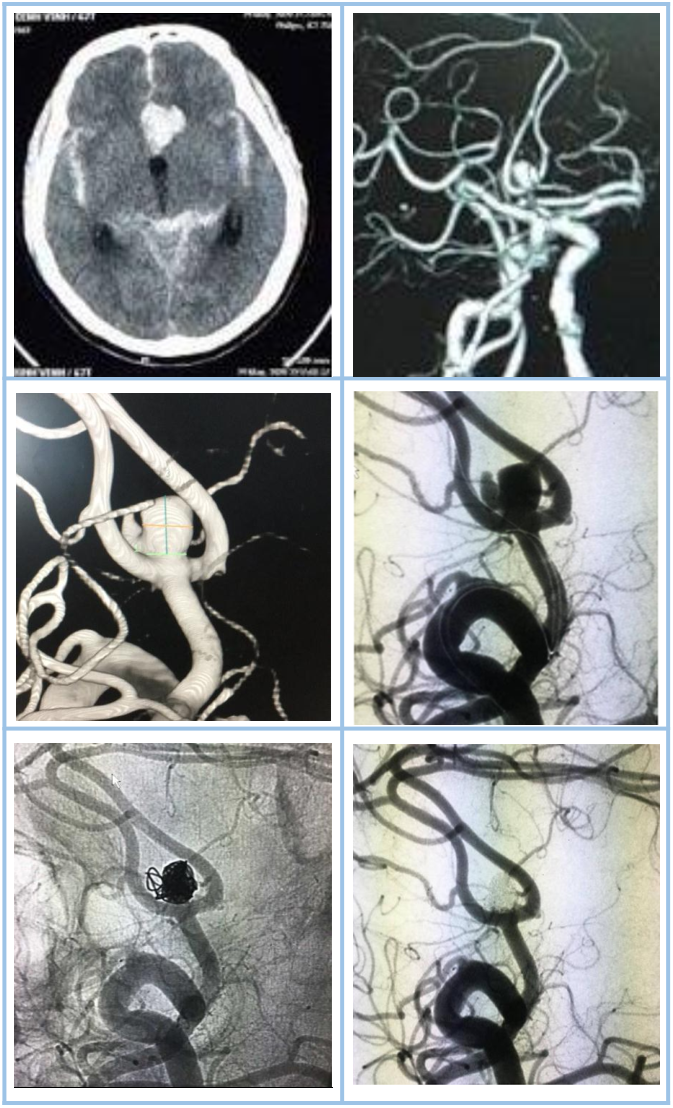

Túi phình động mạch

Bệnh nhân nam 67 tuổi có xuất huyết dưới nhện lan tỏa (Fisher 4) do vỡ túi phình thông trước (phát hiện bằng CT mạch máu). Túi phình sau đó được can thiệp nút tắc hoàn toàn bằng coils có bóng hỗ trợ.